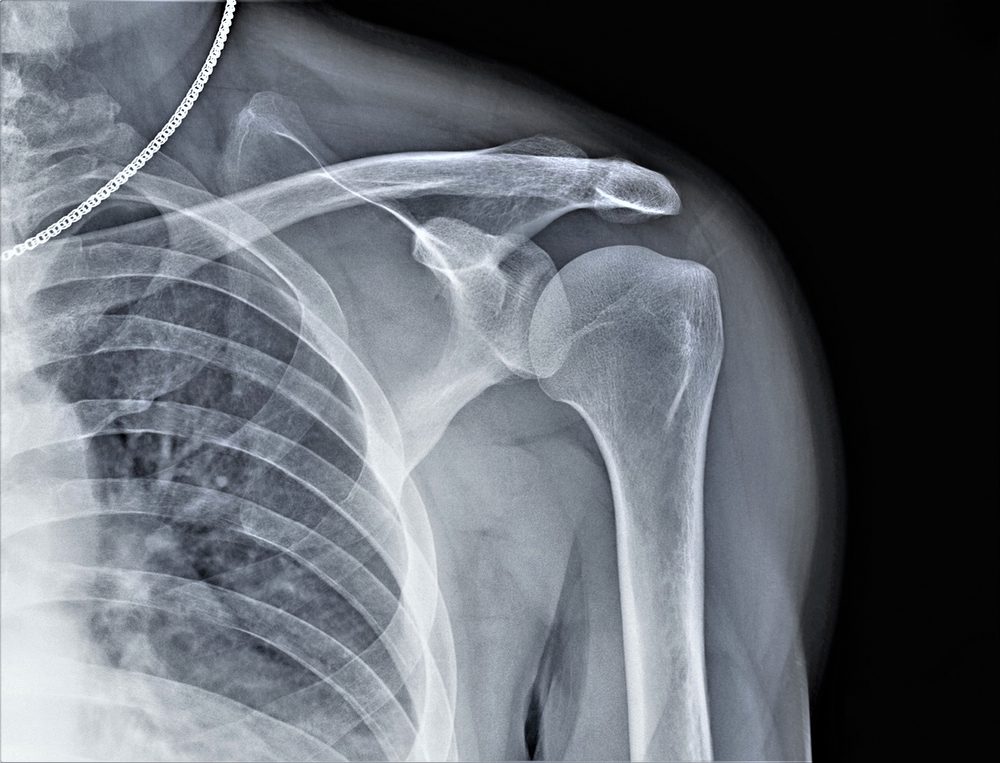

Testosterone helps in the regulation of bone density. Your bones could become less dense if you go through andropause. This can develop into osteoporosis, a condition that affects your bones. They get fragile and frail, allowing them to fracture more quickly.

Osteoporosis can not always present obvious symptoms. You may not realize you have the condition unless you experience an atypical bone fracture or take a standard screening test. If your doctor thinks you have it, he or she may perform a bone density test. They may also conduct a blood test to determine your testosterone levels.